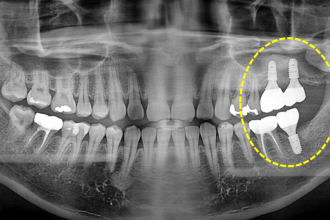

임플란트